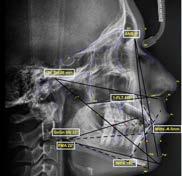

Estudios iniciales radiográficos de inicio

En la radiografía lateral de cráneo ( Figura 6 ) se ve la línea estética de Rickets, que el labio superior se encuentra a +0.5 mm y el inferior a -2 mm. En las mediciones cefalométricas más importantes en la figura 11 un ANB de 5º, GoGn-SN de 33º y FMA de 21º crecimiento normodivergente y Witts de -1 mm. A los criterios dentales encontramos

1-PLT de 129º e IMPA 99º proinclinación de incisivos tanto superiores como inferiores. En la radiografía panorámica (Figura 7), la presencia de 32 órganos dentarios, con terceros molares inferiores aún sin erupcionar y terceros molares superiores

Figura 6. Rx. cráneo lateral inicio progreso con trazos.

Secuencia de radiografías laterales de cráneo (Figura 15) vemos que el ANB disminuyo 1º de inicio a fin clase I con tendencia a clase II esquelética a final. Reducción de Witts 0.5 mm final, crecimiento normodivergente. Mandíbula más pequeña que el maxilar, cambio por el avance mandibular.

Referente a los criteriso dentales, el incisivo maxilar respecto a su base ósea tuvo una importante retroinclinación, inció en 129º y finalizó en 111º, en cuanto al incisivo inferior, este se proinclinó 1º, de 99º a 100º.